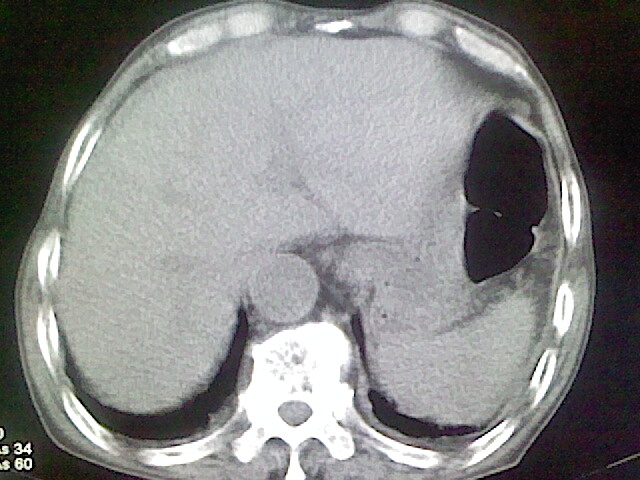

以下是引用zsl6918在2008-8-28 16:49:00的发言:[br]双肺炎性病灶,食管狭窄估计与心房增大压迫所致。

以下是引用xulianj在2008-8-28 20:36:00的发言:[br]慢支肺气肿伴感染,右上肺陈旧性结核;食道建议胃镜检查。

以下是引用wqs571018在2008-8-28 21:18:00的发言:[br]慢支继发感染,右上肺陈旧性结核;食道建议胃镜检查。